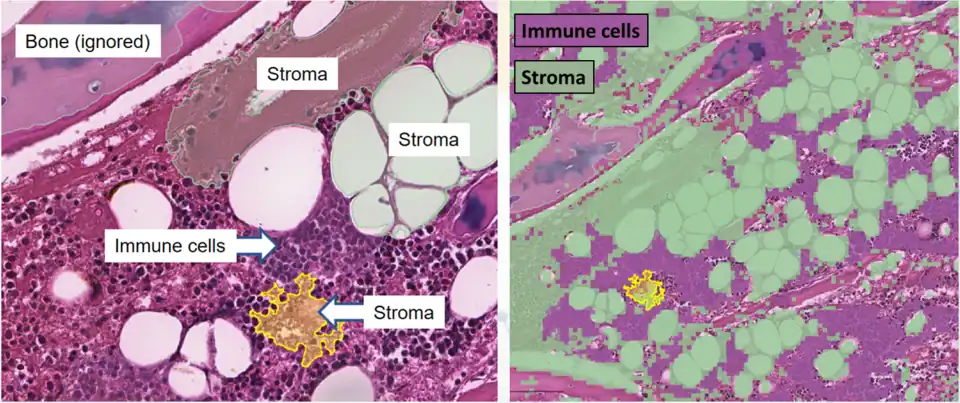

Tissue segmentation for digital calculation of bone marrow cellularity in QuPath: The system is trained on the appearance of immune cells versus other tissue, and uses this to give an overall percentage of each type.

Tissue segmentation for digital calculation of bone marrow cellularity in QuPath: The system is trained on the appearance of immune cells versus other tissue, and uses this to give an overall percentage of each type. -